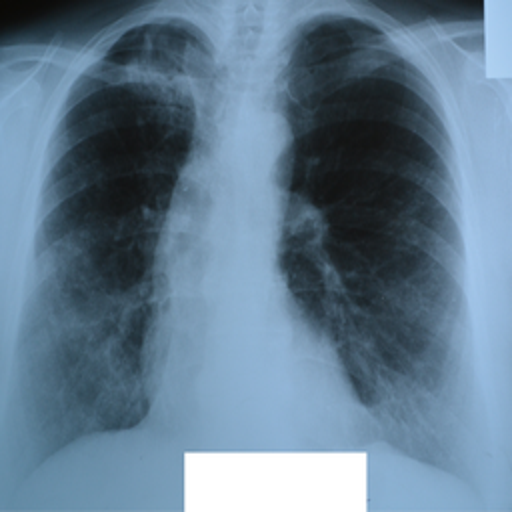

TB Positive X-ray

High Risk TB Prob: 87.5%

Classic Upper Lobe TB

Male, 45y • Persistent cough, night sweats, fever

Cavitation in the right upper lobe with surrounding consolidation. Model confidence: 87.5% TB probability.

CavitationInfiltration